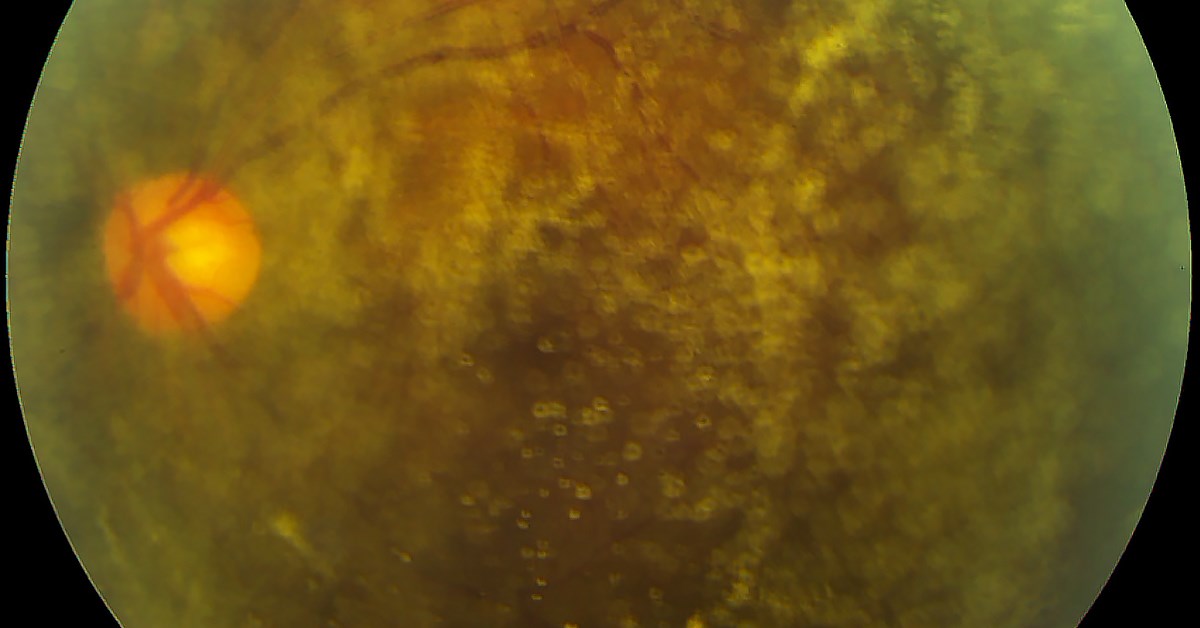

“Smart” contact lenses may someday be used to monitor patients’ eye health. A team of scientists in South Korea packed incredibly small electronic circuitry, batteries, and an antenna into a soft contact lens, which can continuously screen eye fluids for telltale signs of early eye disease, or illnesses such as Diabetes. Although initial tests in humans and rabbits have been promising, a large scale trial on humans has not yet been conducted. This research holds tremendous potential in innovating the ways we detect and prevent potentially blinding eye diseases in the future. Learn more at http://bit.ly/2GpRt5b